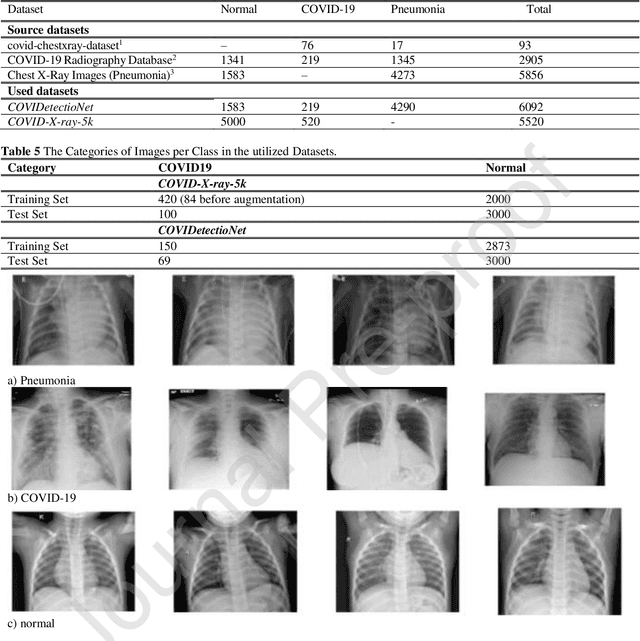

Abstract:Real-time detection of COVID-19 using radiological images has gained priority due to the increasing demand for fast diagnosis of COVID-19 cases. This paper introduces a novel two-phase approach for classifying chest X-ray images. Deep Learning (DL) methods fail to cover these aspects since training and fine-tuning the model's parameters consume much time. In this approach, the first phase comes to train a deep CNN working as a feature extractor, and the second phase comes to use Extreme Learning Machines (ELMs) for real-time detection. The main drawback of ELMs is to meet the need of a large number of hidden-layer nodes to gain a reliable and accurate detector in applying image processing since the detective performance remarkably depends on the setting of initial weights and biases. Therefore, this paper uses Chimp Optimization Algorithm (ChOA) to improve results and increase the reliability of the network while maintaining real-time capability. The designed detector is to be benchmarked on the COVID-Xray-5k and COVIDetectioNet datasets, and the results are verified by comparing it with the classic DCNN, Genetic Algorithm optimized ELM (GA-ELM), Cuckoo Search optimized ELM (CS-ELM), and Whale Optimization Algorithm optimized ELM (WOA-ELM). The proposed approach outperforms other comparative benchmarks with 98.25% and 99.11% as ultimate accuracy on the COVID-Xray-5k and COVIDetectioNet datasets, respectively, and it led relative error to reduce as the amount of 1.75% and 1.01% as compared to a convolutional CNN. More importantly, the time needed for training deep ChOA-ELM is only 0.9474 milliseconds, and the overall testing time for 3100 images is 2.937 seconds.

Abstract:The COVID19 pandemic globally and significantly has affected the life and health of many communities. The early detection of infected patients is effective in fighting COVID19. Using radiology (X-Ray) images is perhaps the fastest way to diagnose the patients. Thereby, deep Convolutional Neural Networks (CNNs) can be considered as applicable tools to diagnose COVID19 positive cases. Due to the complicated architecture of a deep CNN, its real-time training and testing become a challenging problem. This paper proposes using the Extreme Learning Machine (ELM) instead of the last fully connected layer to address this deficiency. However, the parameters' stochastic tuning of ELM's supervised section causes the final model unreliability. Therefore, to cope with this problem and maintain network reliability, the sine-cosine algorithm was utilized to tune the ELM's parameters. The designed network is then benchmarked on the COVID-Xray-5k dataset, and the results are verified by a comparative study with canonical deep CNN, ELM optimized by cuckoo search, ELM optimized by genetic algorithm, and ELM optimized by whale optimization algorithm. The proposed approach outperforms comparative benchmarks with a final accuracy of 98.83% on the COVID-Xray-5k dataset, leading to a relative error reduction of 2.33% compared to a canonical deep CNN. Even more critical, the designed network's training time is only 0.9421 milliseconds and the overall detection test time for 3100 images is 2.721 seconds.